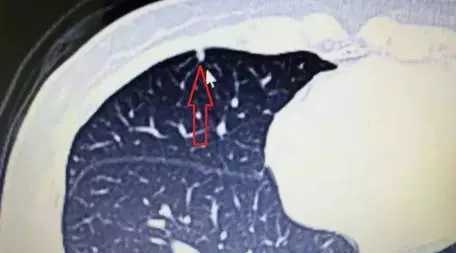

下图配上典型的实性结节和磨玻璃结节,供大家参考。

图片2:典型的肺磨玻璃结节(GGN),为早期肺腺癌